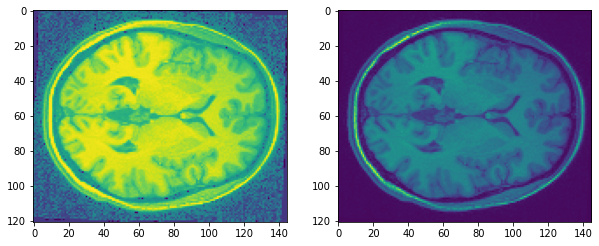

def histogram_equalization(image, min_target_range = None, max_target_range = None, use_target_range = True): ''' Histogram equalization of scalar images whose single channel has an integer type. The goal is to map the original intensities so that resulting histogram is more uniform (increasing the image's entropy). Args: image (SimpleITK.Image): A SimpleITK scalar image whose pixel type is an integer (sitkUInt8,sitkInt8... sitkUInt64, sitkInt64). min_target_range (scalar): Minimal value for the target range. If None then use the minimal value for the scalar pixel type (e.g. 0 for sitkUInt8). max_target_range (scalar): Maximal value for the target range. If None then use the maximal value for the scalar pixel type (e.g. 255 for sitkUInt8). use_target_range (bool): If true, the resulting image has values in the target range, otherwise the resulting values are in [0,1]. Returns: SimpleITK.Image: A scalar image with the same pixel type as the input image or a sitkFloat64 (depending on the use_target_range value). ''' arr = sitk.GetArrayViewFromImage(image) i_info = np.iinfo(arr.dtype) if min_target_range is None: min_target_range = i_info.min else: min_target_range = np.max([i_info.min, min_target_range]) if max_target_range is None: max_target_range = i_info.max else: max_target_range = np.min([i_info.max, max_target_range]) min_val = arr.min() number_of_bins = arr.max() - min_val + 1 # using ravel, not flatten, as it does not involve memory copy hist = np.bincount((arr-min_val).ravel(), minlength=number_of_bins) cdf = np.cumsum(hist) cdf = (cdf - cdf[0]) / (cdf[-1] - cdf[0]) res = cdf[arr-min_val] if use_target_range: res = (min_target_range + res*(max_target_range-min_target_range)).astype(arr.dtype) return sitk.GetImageFromArray(res) #cast the images to int16 because data[0] is float32 and the histogram equalization only works #on integer types. output = histogram_equalization(sitk.Cast(inputimg,sitk.sitkInt32))AHE를 나의 brain data에 대해서 적용해보았을 때의 이미지 결과는 아래와 같다. 오른쪽이 processing을 하기 전, 왼쪽이 processing을 한 이후이다. 전반적으로 object이 존재하지 않는 pixel에 대해서 노이즈가 많이 낀 것을 볼 수 있다. 찾아보니 AHE 단점 중 의미없는 지역의 pixel intensity값이 enhance되어 이미지 왜곡이 생길 수 있다고 한다.